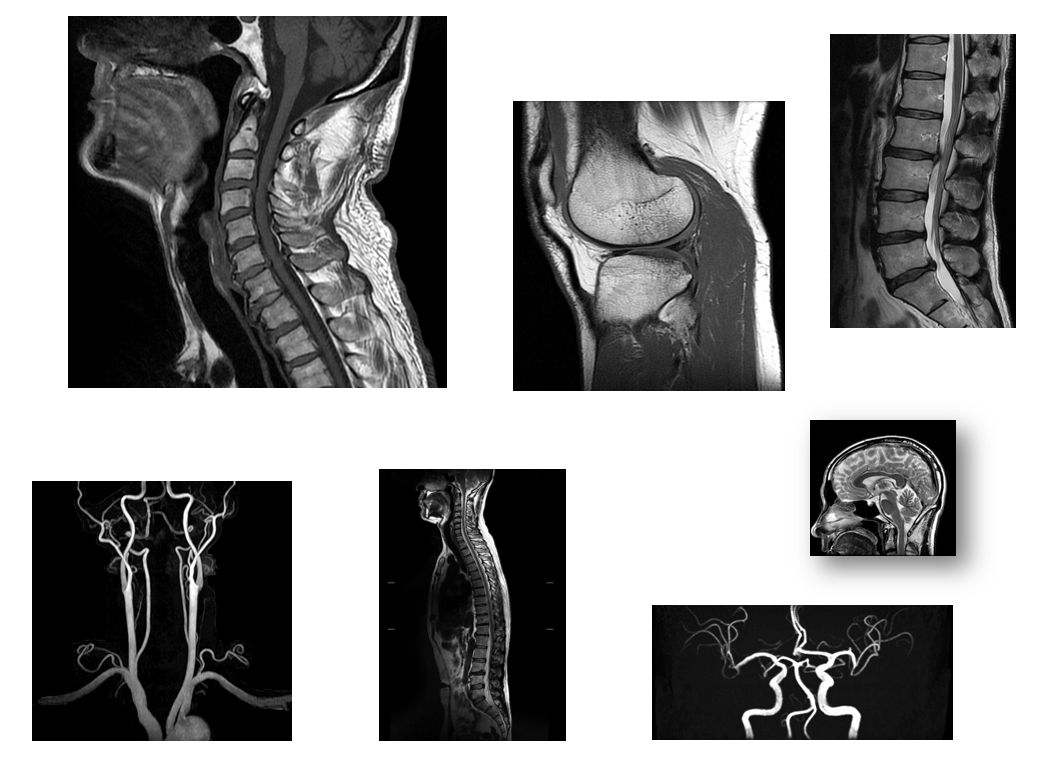

MRI装置